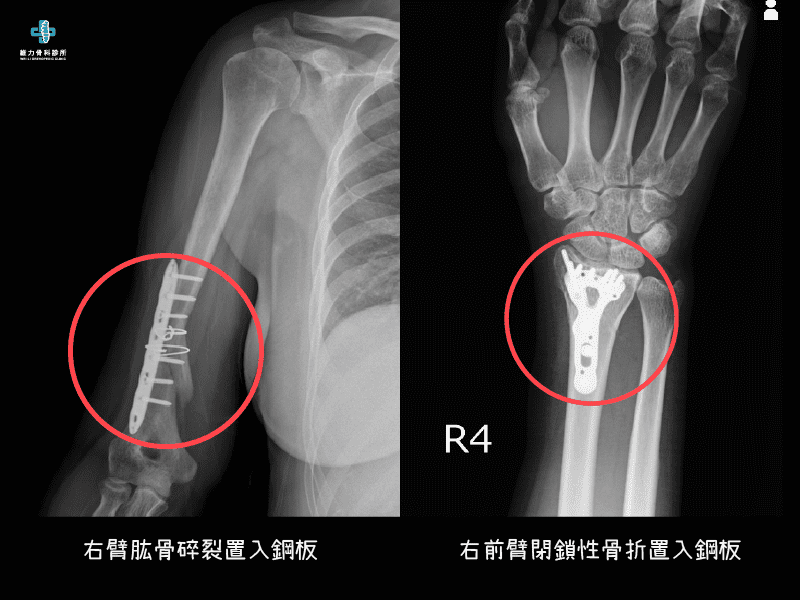

- 粉碎性骨折(Comminuated fracture):嚴重外力使骨頭破裂成細粉狀(需注意造成腔室症候群)。

- 閉鎖性骨折:又稱為簡單骨折,指的是斷骨未凸出皮膚表面(需注意造成腔室症候群)。

骨折的治療目的在將骨頭儘可能恢復至原來位置或可接受的位置,傳統會使用石膏固定或開刀後以骨釘或鋼板固定。治療的方式會因為骨折的型態、位置、病人的需求而有所不同。一般的壓迫性骨折,多發生在脊椎位置,可分為保守治療與開刀治療